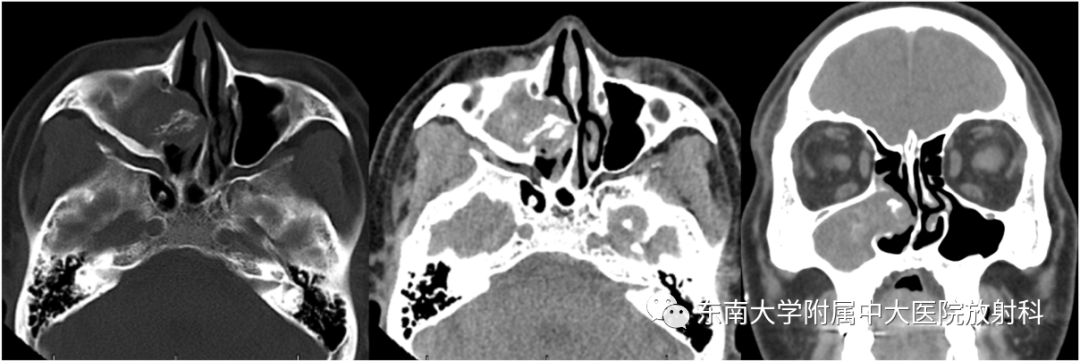

真菌性鼻窦炎

病史

男,50岁

主诉:右侧鼻腔反复流脓涕10年

手术史:患者20年前因“鼾症”于当地医院行“咽部手术及鼻中隔矫正术”,术后恢复可